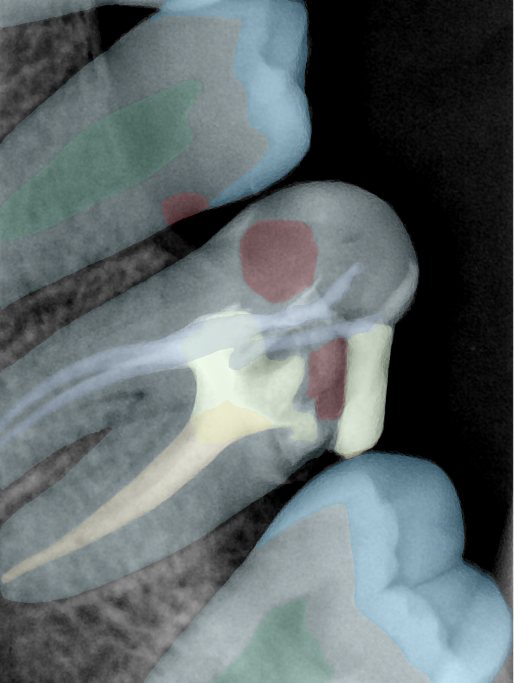

CR/DR 牙齿分割阶段记录

当前进展

- 完成了 CR/DR 牙齿相关分割训练

- 当前结果已经达到阶段预期,但仍有细节问题需要继续处理

相关测试

遇到的问题

- 训练过程中出现过 mask 下移问题

- 部分结果会出现 box 填充异常

- mask 边缘仍然有比较明显的锯齿感